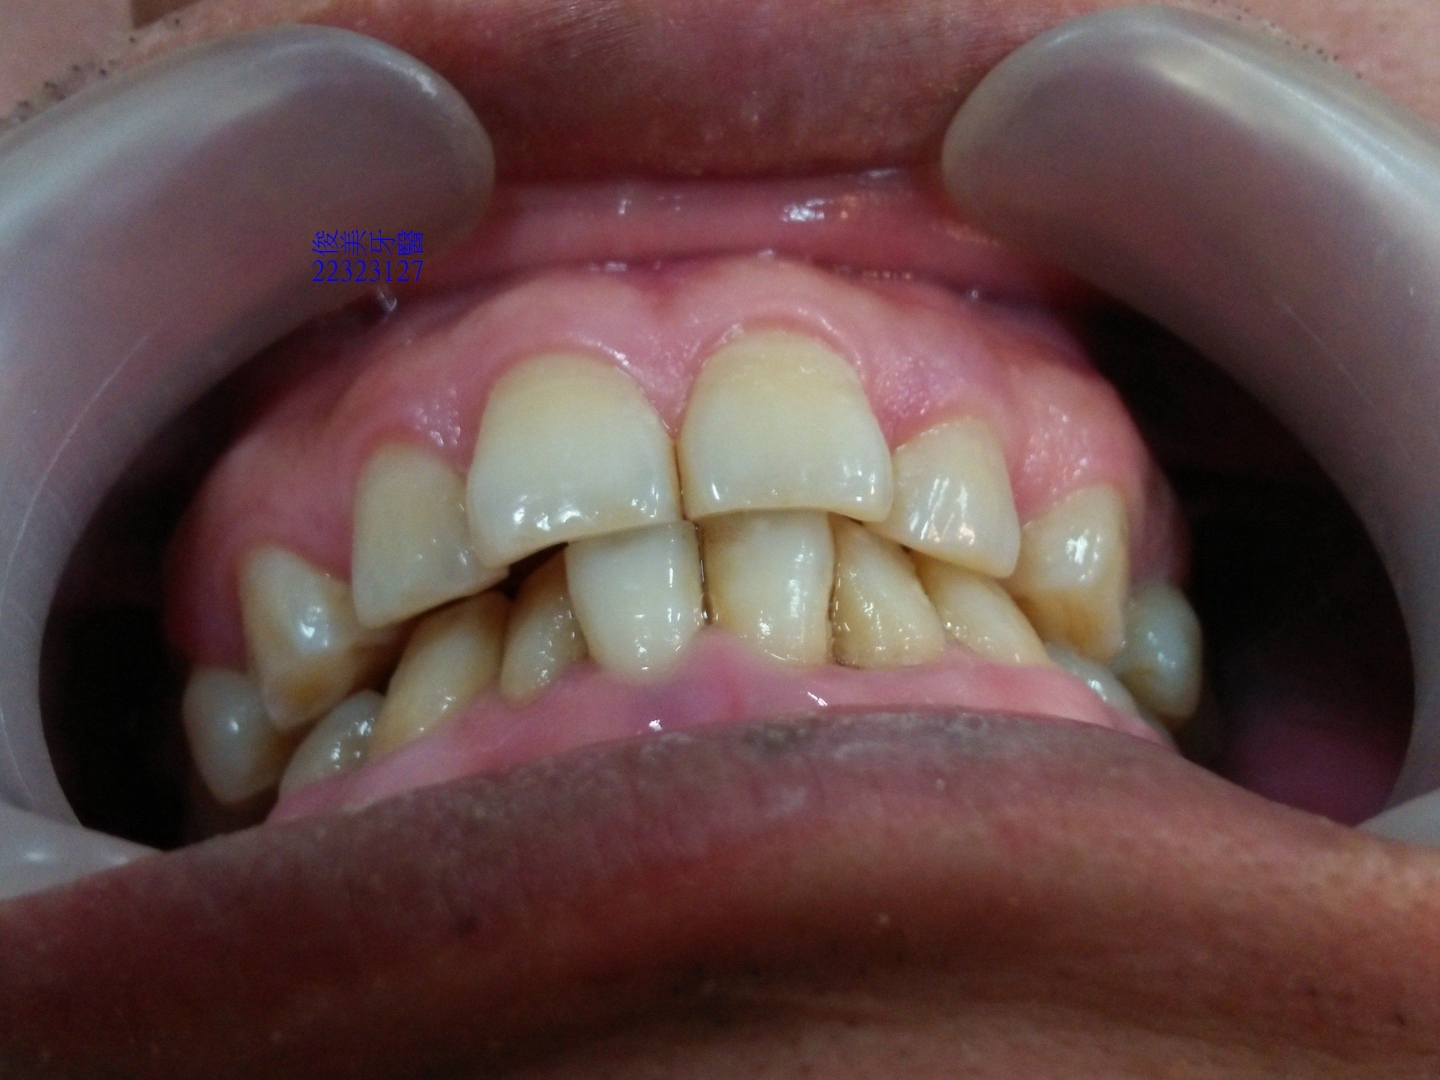

牙齒位移,前牙受力明顯過多,牙齒磨損的很平,牙齒變短、切端變厚。

牙縫開始變大。

上顎原始狀況。

後牙咬合高度逐漸變低。

後牙咬合高度逐漸變低;犬齒受力大,高度剩下2/3,切端皆已磨損喪失。